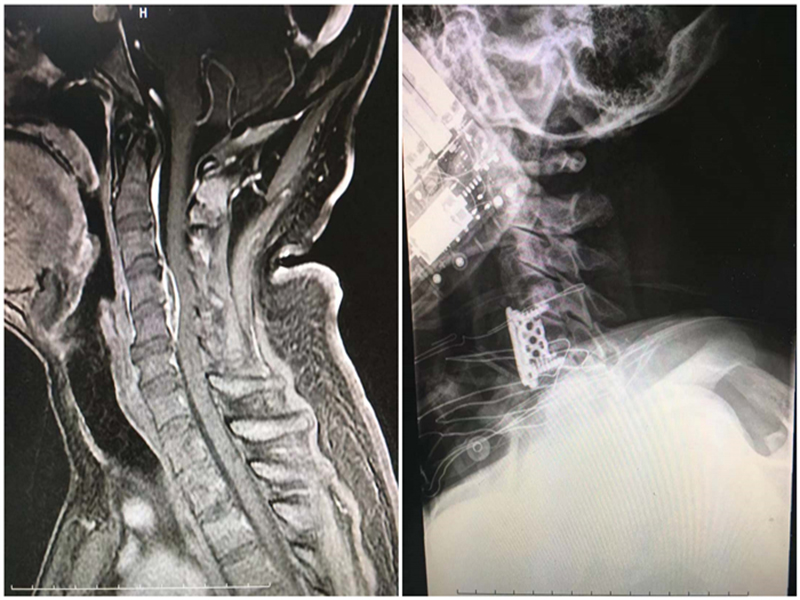

4 -5 4 -5 ( 1 )

45 2 ( 0 ) 4 - 5 3